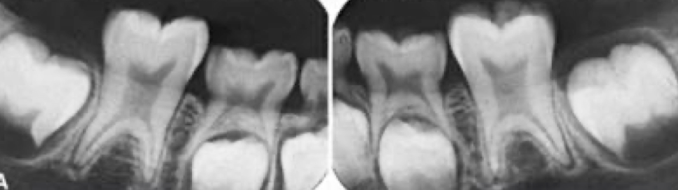

What dental anomaly is this?

dilaceration